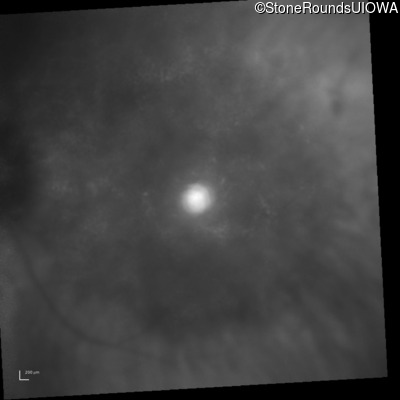

Infrared Fundus Photograph - Right - 20/80 +1

Exemplar